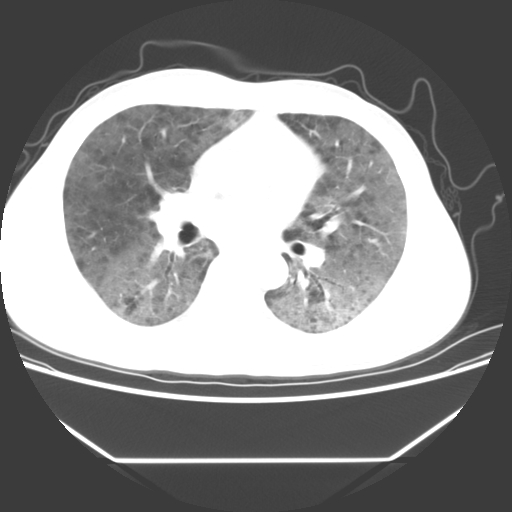

病人55岁,咳嗽,胸闷

忘了传病史了,病人55岁,咳嗽,胸闷

两肺部呈“毛玻璃”状改变,原因待查考虑感染性病变

病人是否发烧,两肺“磨玻璃”影,其间见空气支气管征和碎路石征。考虑肺泡蛋白沉着症。

两肺广泛对称磨玻璃样影,密度不均,考虑机遇性肺部感染。

双肺弥漫磨玻璃样病变,病史很重要。有感冒或发烧史,甲流不除外。无发烧可考虑肺泡蛋白沉积,但肺泡蛋白沉积边缘往往较清晰,与正常肺组织分界清晰

两肺弥漫间质性病变,考虑肺泡蛋白沉着症。建议进一步检查。

两肺“磨玻璃”影,其间见空气支气管征和碎路石征。考虑肺泡蛋白沉着症。